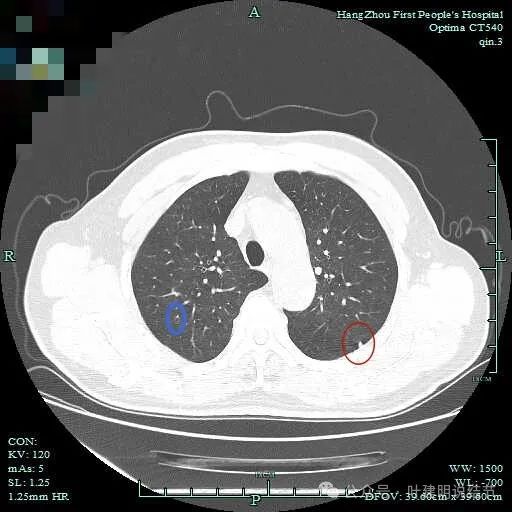

次病灶连续层面观察:

紧贴脊柱处混合密度,趴在脊柱上,这不像结节状。

但有小血管似的,磨玻璃部分界限较清。但此类异常影像在正常人的CT上也挺常见。

密度较高,确实像血管进入。但病灶片状,趴在脊柱上。

此层显得更呈小片状了。

与脊柱间似乎有间隙在,另见微小血管进入这条索状的偏高密度影处。

有细小血管进入,但说不上异常增粗。病灶仍是小片状,条状。

磨玻璃成分密度淡且界欠清,整体就是条索状弯曲的。

上图见细毛刺明显。

病灶实性伴细毛刺,与脊柱间有间隙在。

病仍明显,从上到下,觉得应该是成片的。

表面不平毛刺,实性密度为主。

微小血管有,但无异常增粗。

病灶实性,边缘不光滑。

实性密度,片状,条状。

病灶实性,缺乏膨胀性。

上图呈结节状,表面不平,有少许磨玻璃成分。

结节状,密度高,边缘欠光滑。

与脊柱之间有间隙,表面有细毛刺。

表面不平,似有细支气管截断征。

边缘不平毛糙。

像慢性炎似的。

瘤肺边界欠清。

边缘区淡磨玻璃密度。